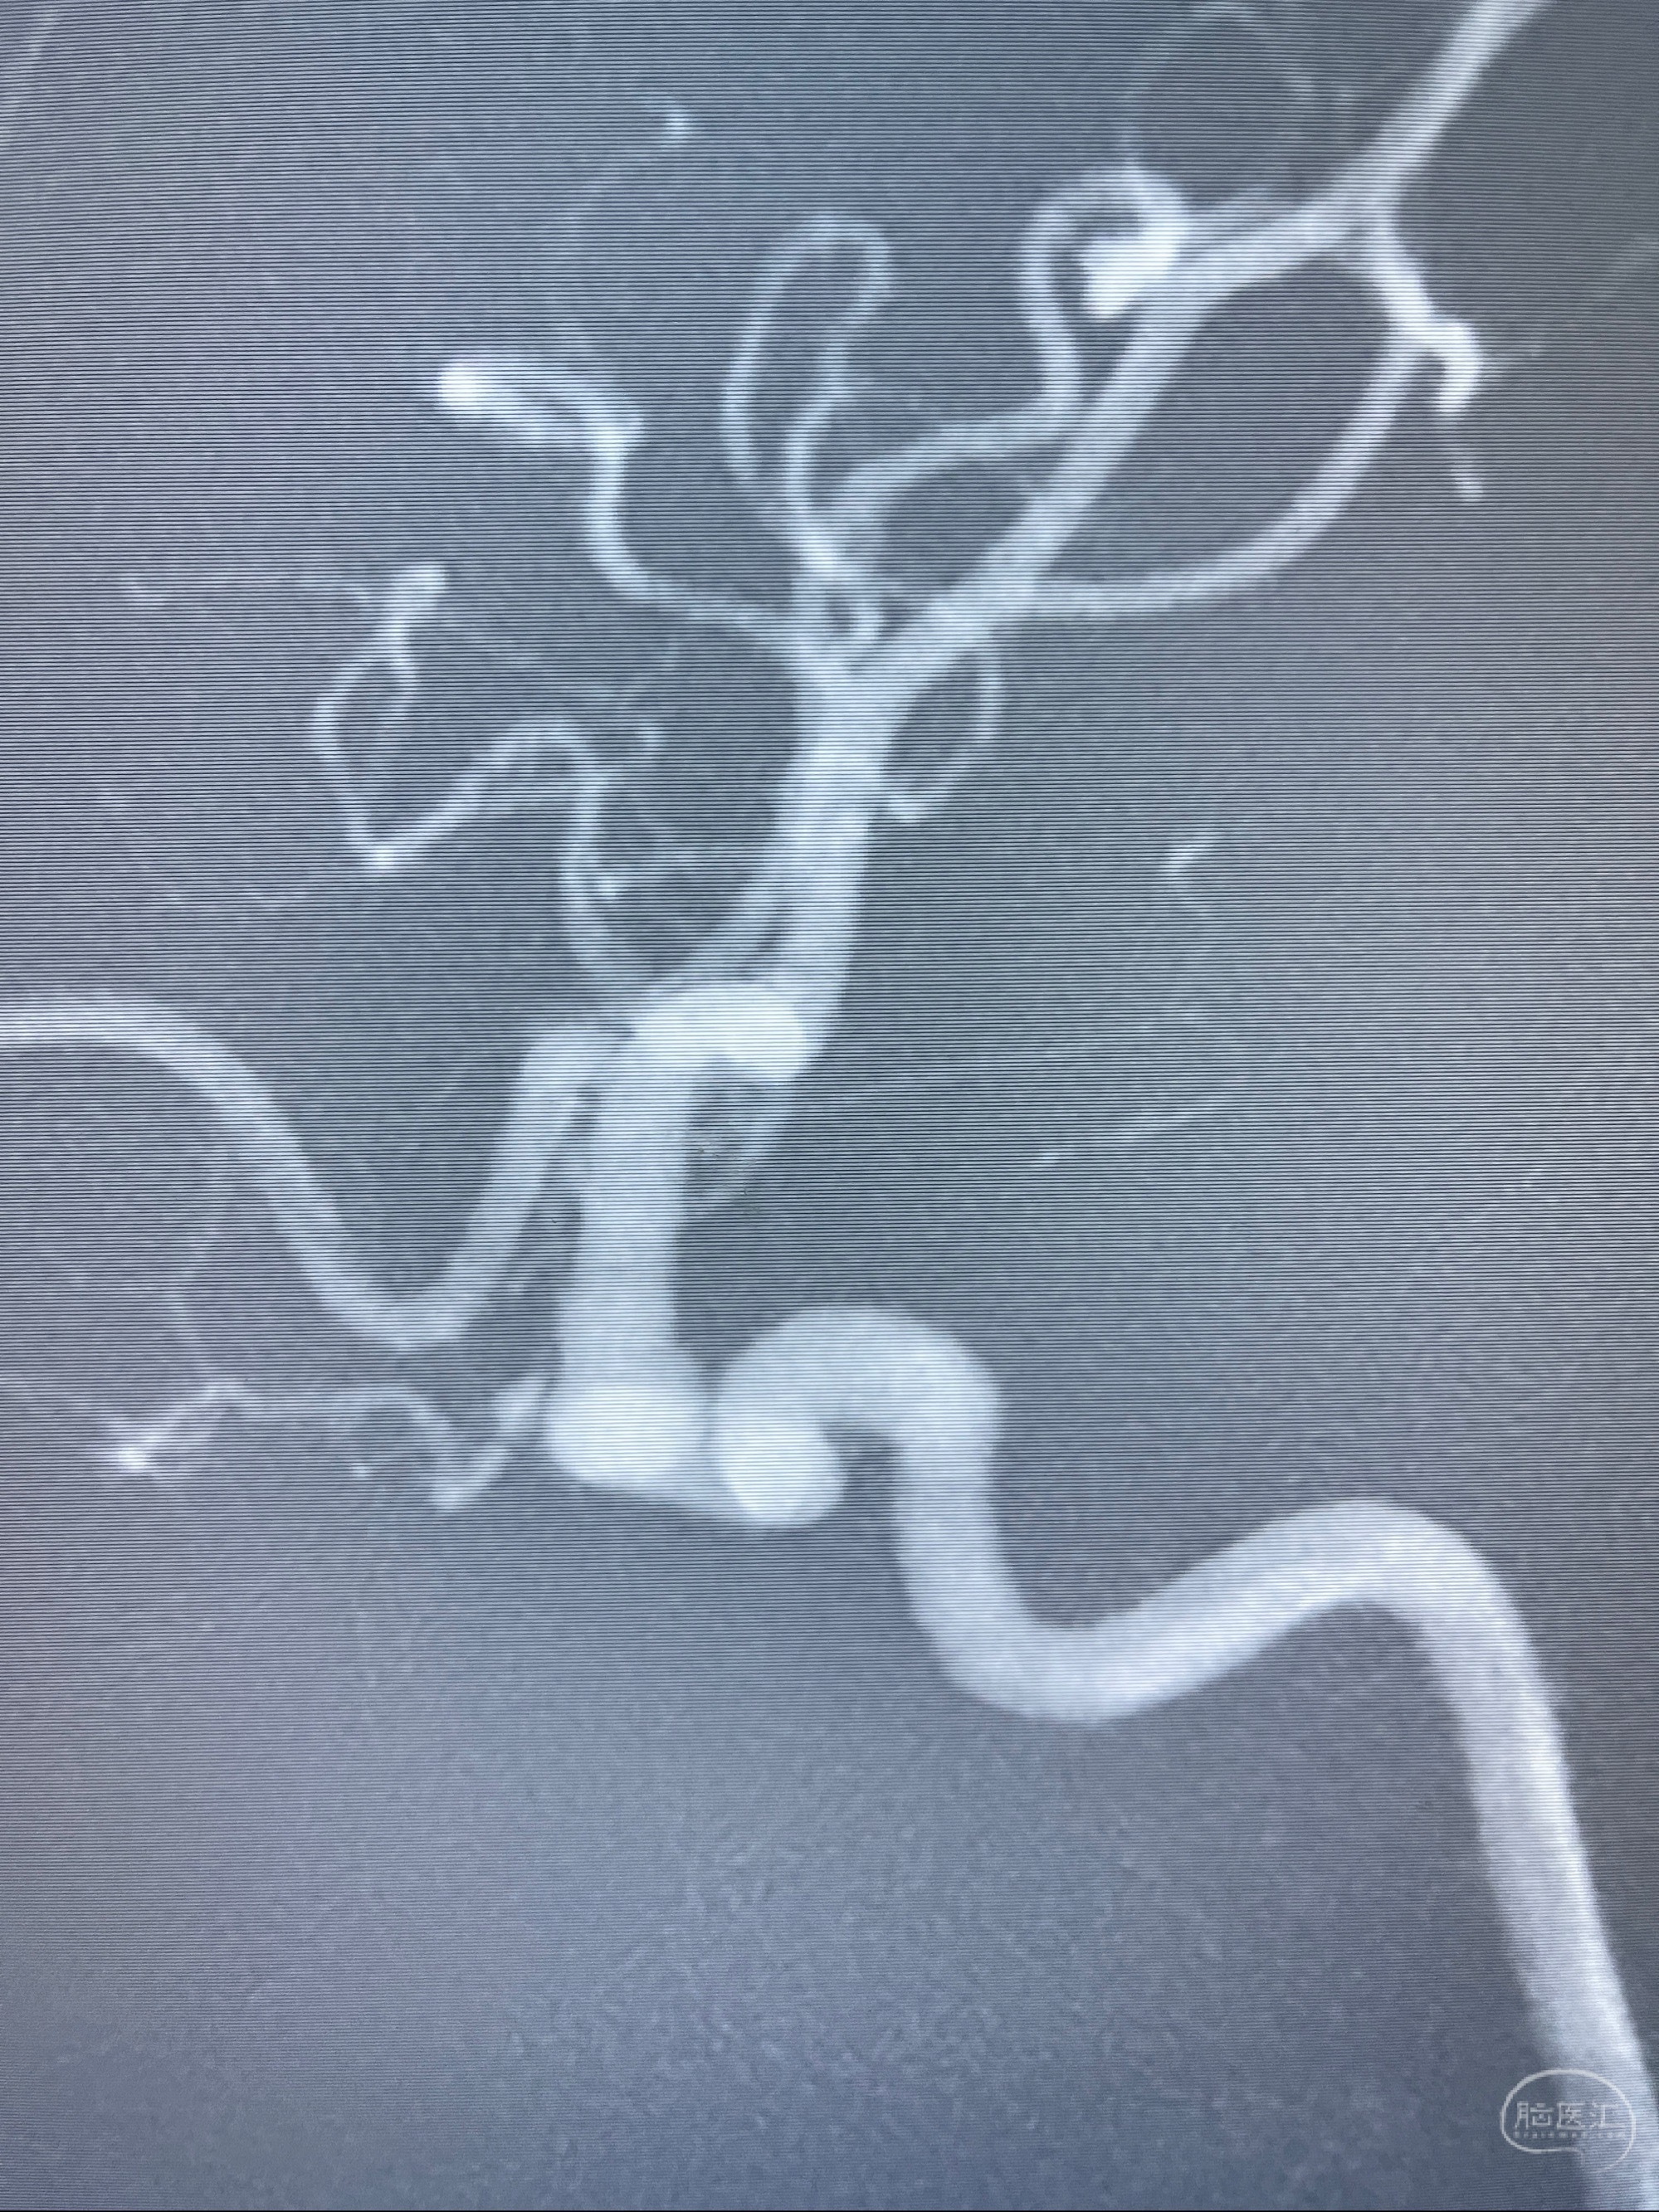

2023.07.25 泰州市人民医院查头颅CTA提示右侧C6段瘤样突起,建议DSA检查;

CTA示:右侧颈内动脉C6段见指向下方的突起,余左侧颈内动脉、双侧椎动脉、大脑前动脉、大脑中动脉、大脑后动脉及基底动脉走形正常,未见明显扩张及狭窄,局部未见明显瘤样扩张。

看原图,应该有两侧动脉瘤😅

2023-07-27全脑血管造影:双侧颈内动脉眼动脉段动脉瘤,右侧较大